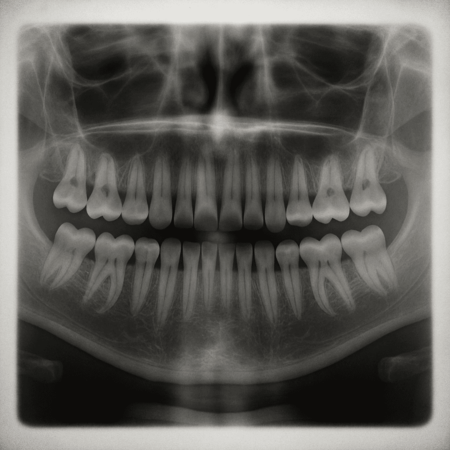

Investigadores del Hospital Kitano en Osaka, Japón, y de la Universidad de Kioto, han comenzado a probar en humanos un fármaco experimental capaz de regenerar dientes pedidos. Los científicos esperan que este medicamento ofrezca una alternativa a las dentaduras postizas y los implantes, y que esté disponible para su uso general a más tardar en 2030.

Como explica Dentistry Today, al inhibir la proteína que produce el gen USAG-1, el cuerpo “recuerda” que tiene la capacidad de generar nuevas piezas dentales. Takahashi explica que los humanos conservamos una tercera generación de dientes en forma de yemas, que normalmente permanecen inactivas. En personas que padecen hiperdoncia, esa capacidad se activa de forma natural.

En 2024, el tratamiento comenzó a probarse en 30 hombres de entre 30 y 64 años que perdieron al menos un diente. A cada uno se le administró el medicamento de manera intravenosa, y el seguimiento durará 11 meses para evaluar su seguridad y efectividad. Hasta ahora, los experimentos previos en animales no han mostrado efectos secundarios, lo que llena de optimismo a los investigadores.